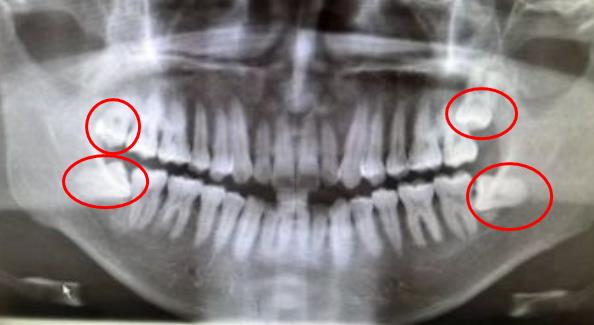

上圖智齒拔牙價(jia) 格僅(jin) 做參考,不作為(wei) 實際診療收費標準